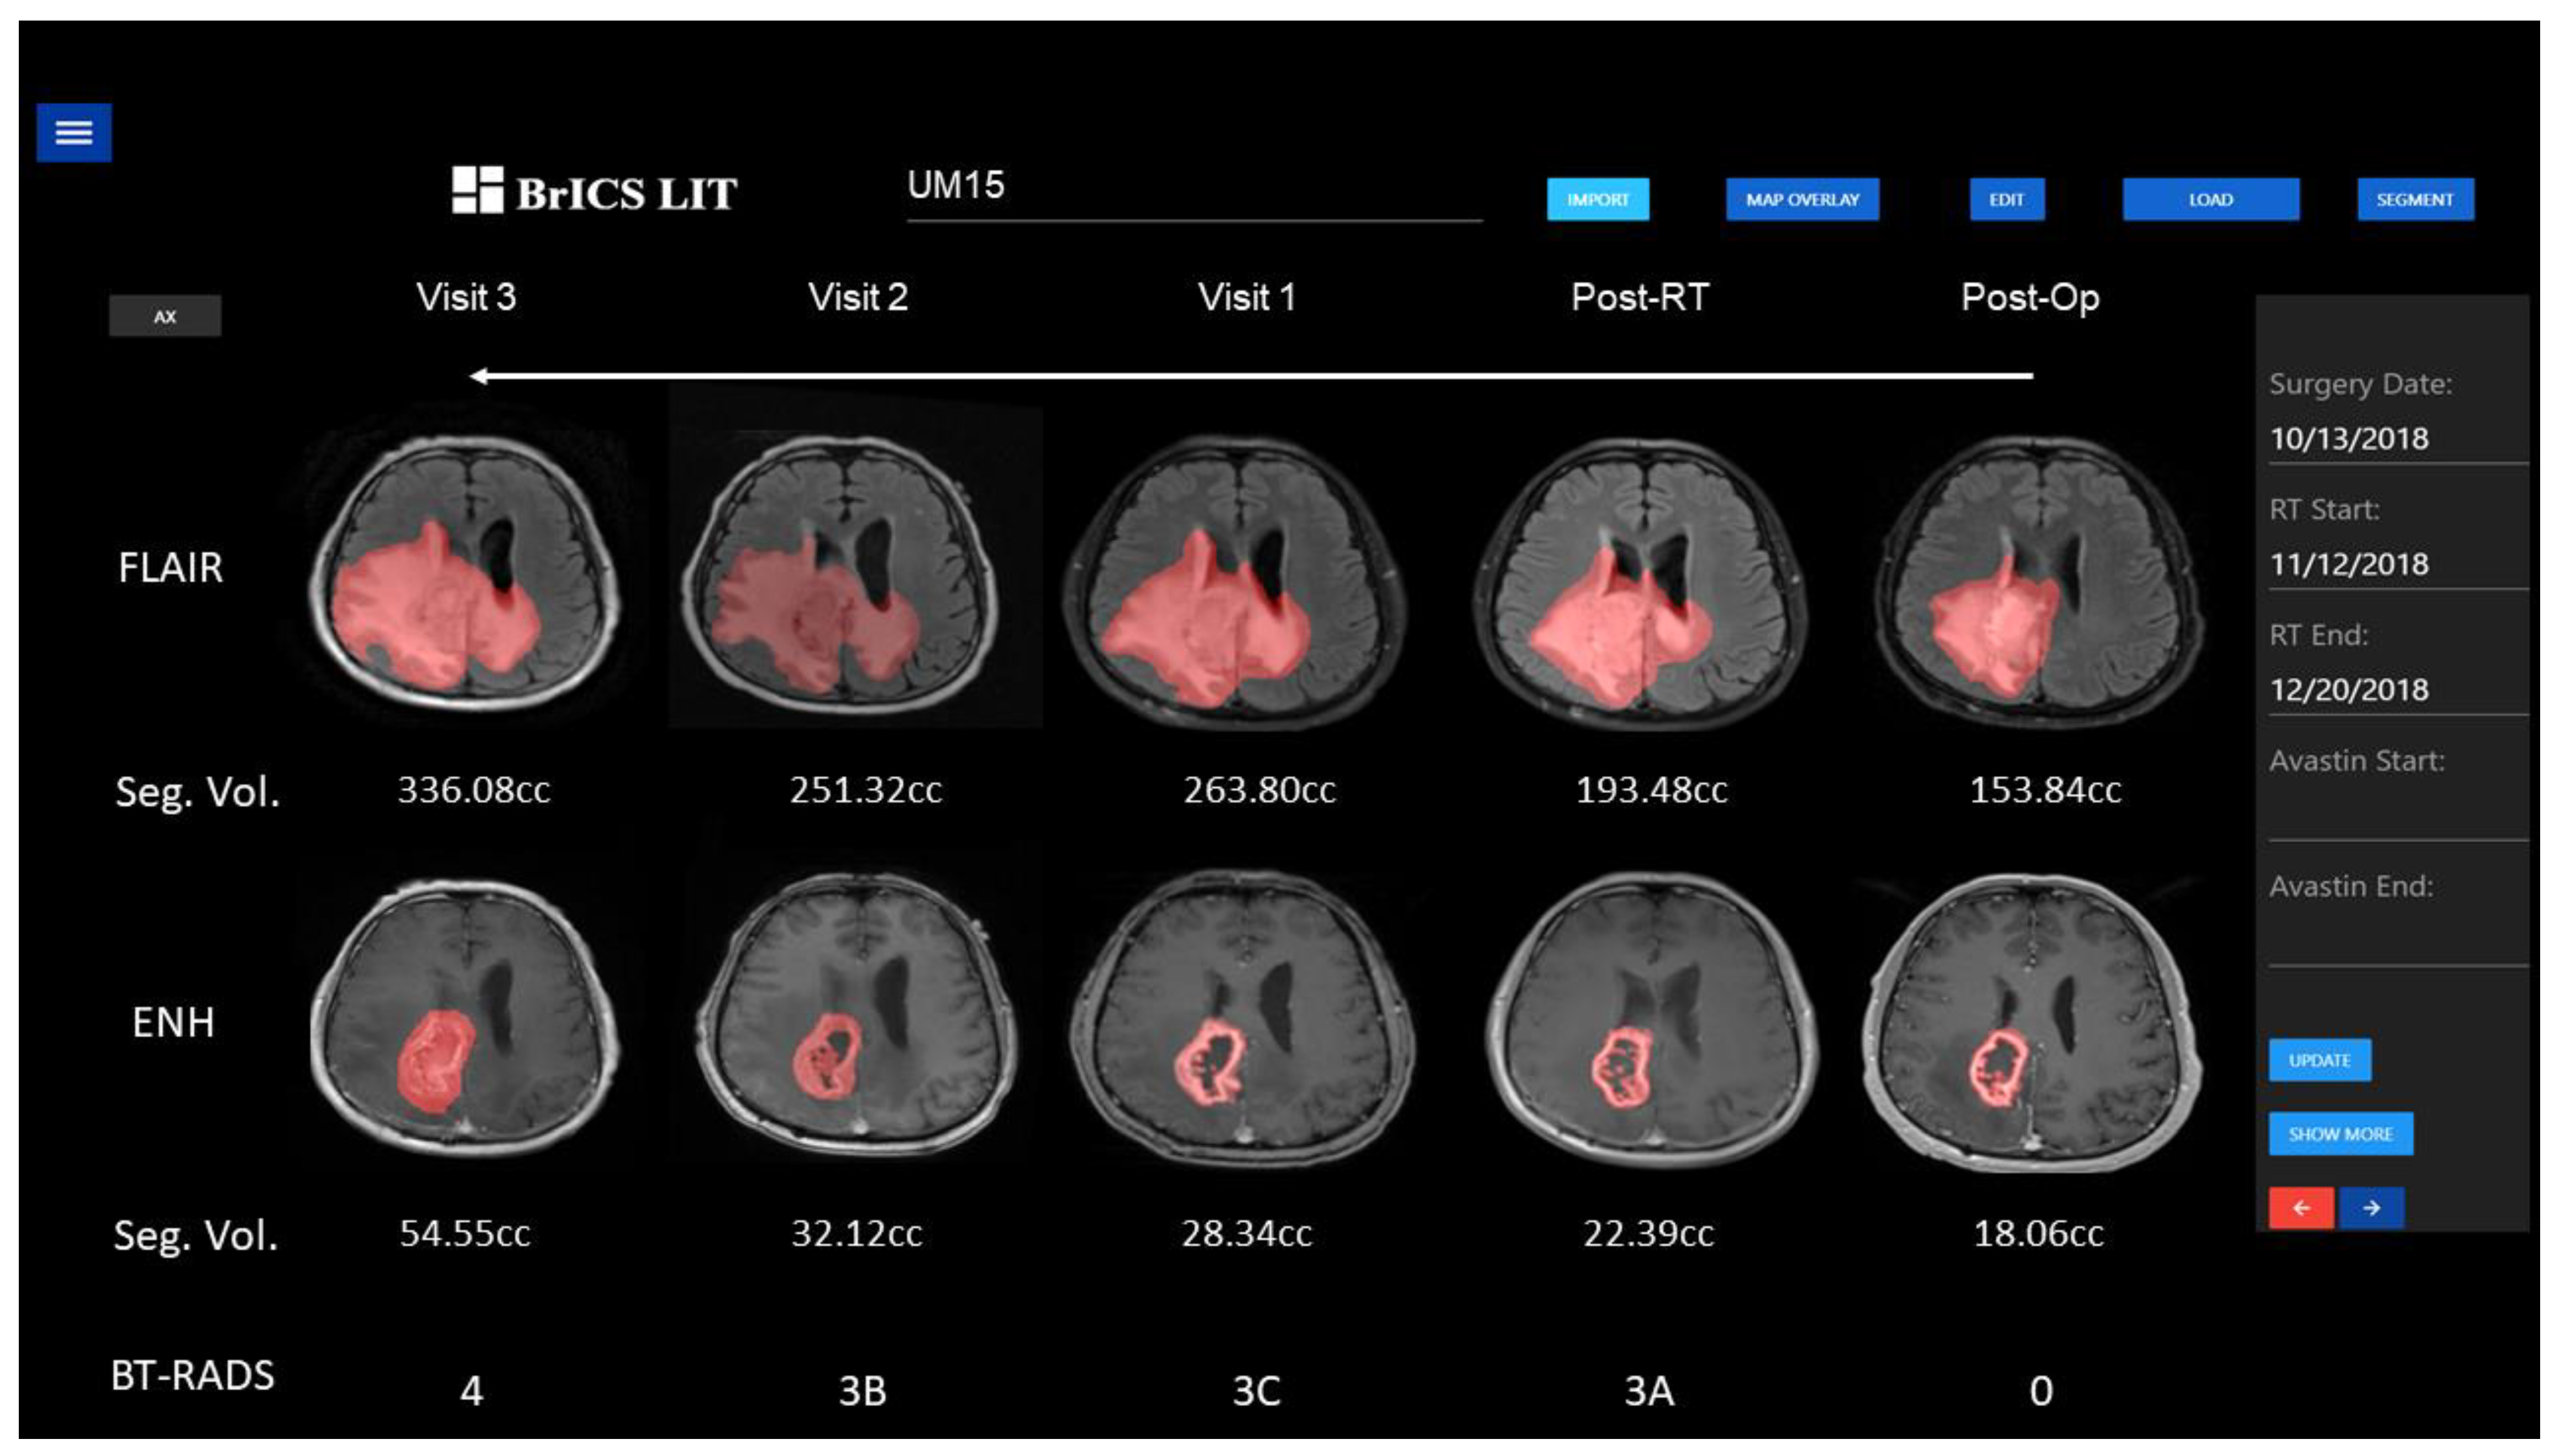

2.3. Application of Segmentation in Longitudinal Tracking

3.2. Application of Segmentation in Longitudinal Tracking